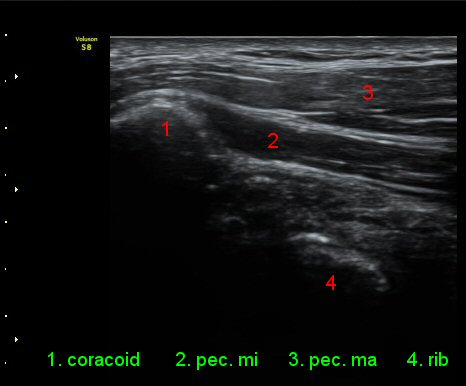

ŽÃËÀÚ¸¦ ¿À±¸µ¹±â ¾Æ·¡·Î ±æ°Ô ´ë°í °üÂûÇÏ´Ï ¿À±¸µ¹±â ¾Æ·¡, ¼ÒÈä±Ù ½ÉÃø¿¡ ¼ö¾×Àú·ù°¡

°üÂûµÇ¾î ¿À±¸µ¹±âÇÏÁ¡¾×³¶¿°À» ½Ã»çÇÑ´Ù(»çÁø 5).